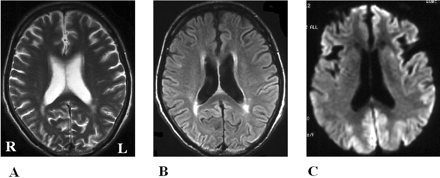

酒后驾驶是在26日检查库贾氏症患者发病后3到25周平均持续时间为10.7周。24库贾氏症患者表现出高强度脑损伤的驾车考试。两个观察者,醉酒驾车的库贾氏症诊断的敏感性为92.3%。interobserver协议率为100%。3例(12.5%)显示只在尾状头和硬膜损伤,10例(41.7%)患者显示线性损伤只有在大脑皮层,和11例(45.8%)患者显示病变基底神经节和大脑皮层(图1)。其中,只有三个病人(12.5%)显示,丘脑病变。没有病人显示高强度在小脑病变。高强度损伤在驾车之前出现脑萎缩。病变包括纹状体初并不总是对称的但是后来对称(图2),尽管对称的纹状体病变是众所周知的在库贾氏症。11在某些情况下,高强度损伤与连续驾车并不总是进展的疾病,而有时信号强度降低了疾病进展的一些病变。在某些情况下,皮质高信号强度不同,解剖分布(图3)。在终端阶段与深刻的脑萎缩,高强度损伤变得不清楚。T2I DWI-examined 26日在23日检查病人,但T2I扫描被排除在外,因为低质量由于运动构件。一位观察家认为11 22患者阳性(50.0%),而另一个观察者认为8阳性(36.4%)。interobserver协议率为68.2%,低于酒后驾车(p< 0.005)。在这两个观察者,醉酒驾车是比T2I更敏感(p一个观察者,< 0.005p另一个观察者p < 0.0005)。天赋是17 26患者的检查。一位观察家认为10 17例阳性(58.8%),和另一个观察者认为7是积极的(41.2%)。interobserver协议率为82.4%,也低于酒后驾车(p< 0.05)。醉酒驾车是比天赋更敏感(p一个观察者,< 0.01p另一个观察者p < 0.0005)。我们在图4一个例子中,只有醉酒驾车可以检测高强度异常病变。

图4。比较显眼的克雅氏病疾病变化相同的病人在不同的核磁共振序列。t2加权成像(A)和fluid-attenuated反转恢复成像(B)显示正常的结果,和diffusion-weighted MRI (C)展示了高强度在大脑皮层病变。